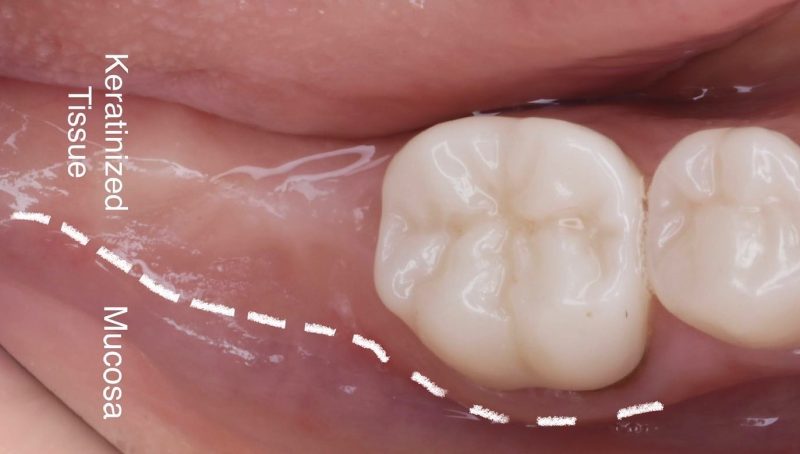

This case highlights the importance of soft tissue management for long-term implant success. In this case, I placed an implant on a healed site for a lower second molar, and my approach focused on ensuring we have a thick keratinized band on the buccal side.

When dealing with these cases, I intentionally make my incision more lingual to preserve as much tissue as possible for the buccal side. I place the implant 1.5mm subcrestal to ensure proper stability and room for bone and soft tissue regeneration. Once the implant is in place, I use a healing cap and reposition the tissue, which allows us to achieve a thick, healthy band of keratinized tissue on the buccal.

This step is crucial because having enough keratinized tissue not only improves aesthetics but also contributes to better hygiene maintenance and long-term implant success.